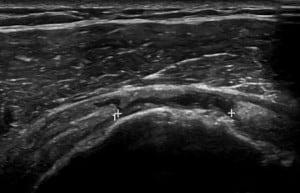

This comprehensive case series webinar focuses on the use of ultrasound for diagnosing shoulder pathologies. Through a series of real clinical cases, participants will learn how to identify common shoulder conditions such as rotator cuff tears, impingement syndrome, biceps tendonitis, labral tears, and osteoarthritis. The session will guide healthcare professionals through the process of performing shoulder ultrasound, interpreting key imaging findings, and distinguishing between various shoulder injuries. Dynamic imaging techniques and tips for assessing structures like the rotator cuff, acromioclavicular joint, and glenohumeral joint will also be covered. This case-based approach is perfect for clinicians seeking to enhance their diagnostic skills and improve patient care in shoulder musculoskeletal ultrasound.

Identify pathology of the rotator cuff on ultrasound